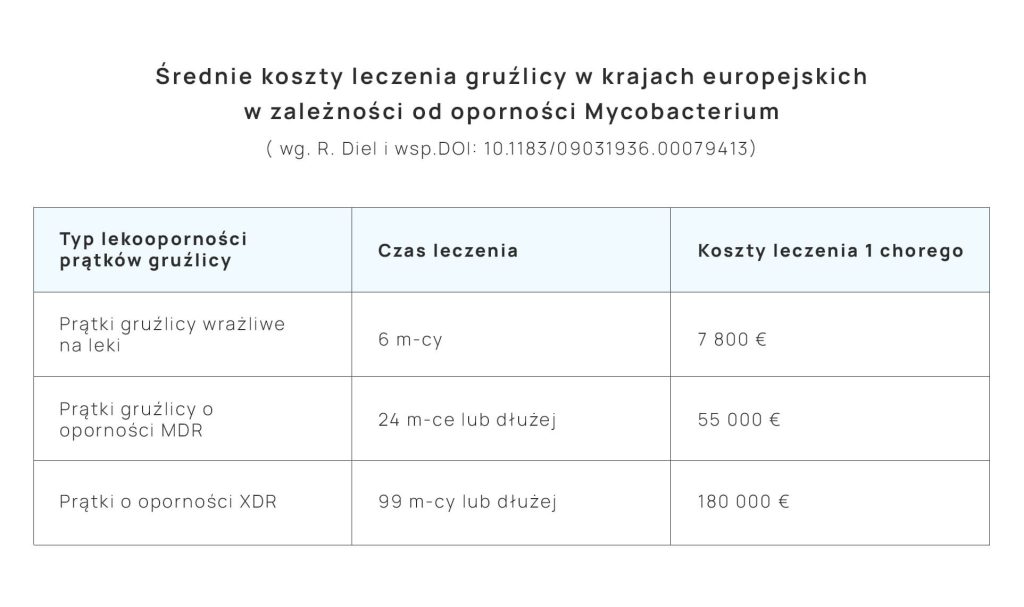

Czas leczenia gruźlicy wrażliwej na leki wynosi 6 miesięcy, a w przypadkach form lekoopornych stosuje się wiele leków (6 lub 7), czasami nawet przez kilka lat . W trakcie leczenia lekarz monitoruje wystąpienie ubocznych objawów stosowanych leków. Odprątkowanie chorego (wyleczenie) musi być potwierdzone metodami mikrobiologicznymi. W tym celu chory oddaje do badania w laboratorium 2 próbki plwociny pobrane w różnych dniach.

Leczenie gruźlicy generuje bardzo wysokie koszty pokrywane z budżetu państwa. Jednak w wielu ubogich krajach, o dużym rozprzestrzenieniu się choroby, oczekuje się, że pacjenci poniosą koszty jej leczenia (korupcja lekowa), co skutkuje przerwami w leczeniu lub całkowitym jego brakiem. Powoduje to powstanie form opornych na leki na gruźlicę, transmisję choroby do ludzi zdrowych i dalsze rozprzestrzenianie się choroby. Ponadto, chorzy często sami przerywają leczenie. Skrócenie schematu leczenia powoduje nawrót prątkowania i szybkie powstanie lekooporności. Takie zjawiska są notowane na całym świecie.

Tabela obrazuje bardzo wysokie koszty leczenia gruźlicy, których nie da się porównać do żadnej innej choroby zakaźnej.